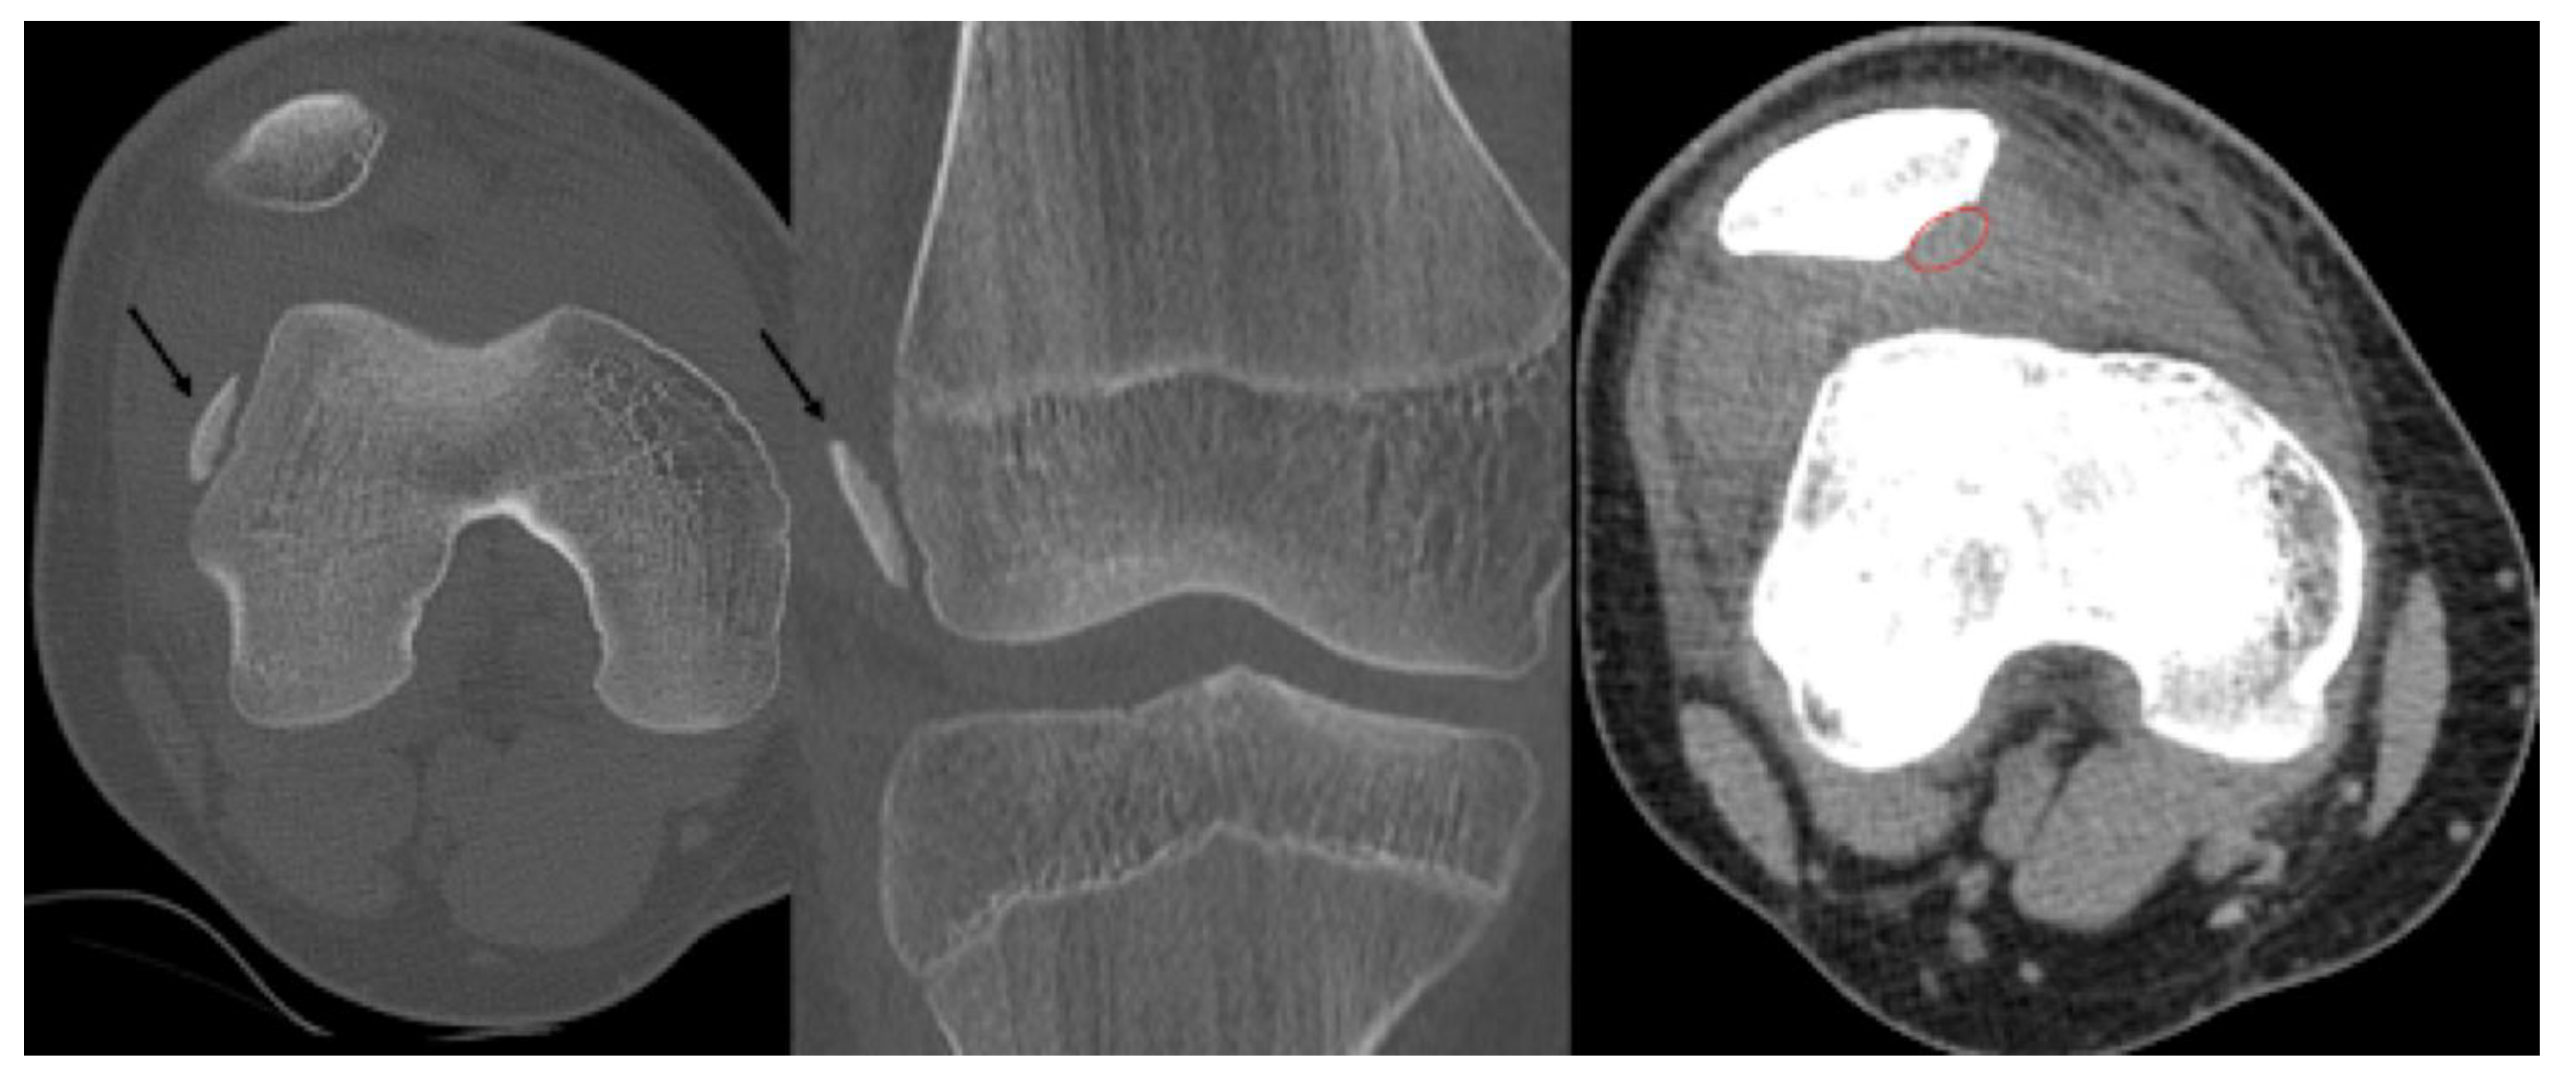

- Type A: Cystic on CT and Edema on MRI

- Type B: Non-displaced and incompletely undercut by fluid (MRI) and lucency (CT) with an open connection to the articular cartilage.

- Subchondral Cyst formation

- X-ray: Secondary Osteoarthritis